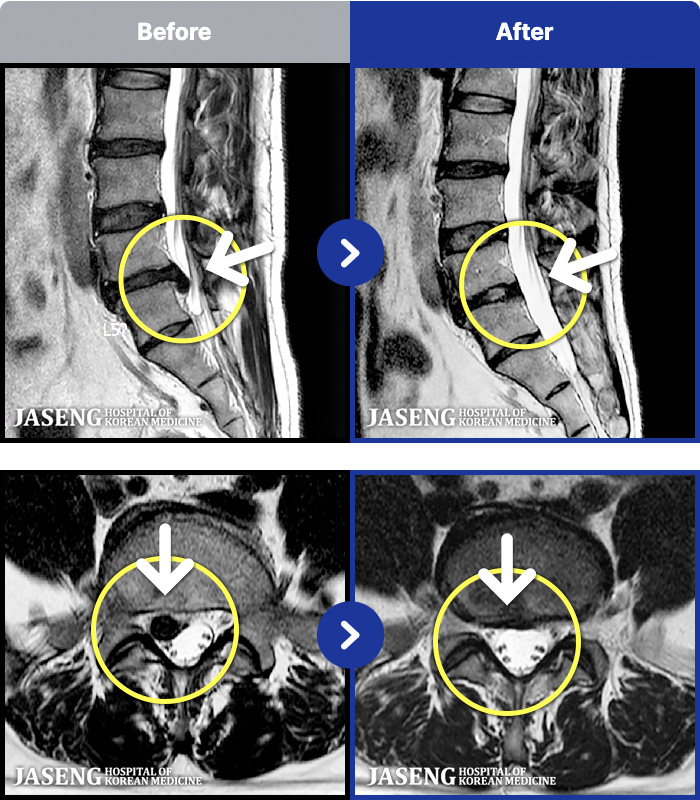

1,237 MRI ũ ʸ Ȯϼ.

1,237